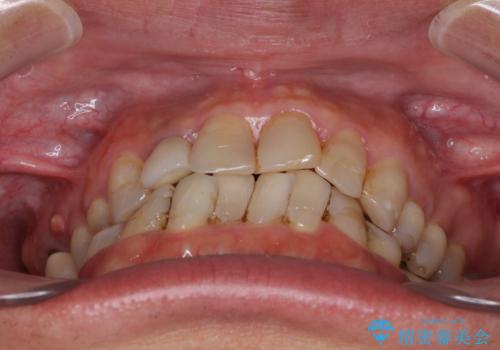

- 前歯のデコボコや、奥歯を咬んだときに痛みがあるとのことで来院された患者様です。

全体的に問題が多く、全てをしっかりと治療したいとのことでした。

全体的に中等度の歯周病と診断されたため、歯周外科処置やインプラントによる咬合回復から進めて行き、矯正治療による歯列改善を行った後にオールセラミッククラウンにて補綴することとしました。

矯正治療を希望して来院されましたが、歯周病を併発していたため、矯正治療開始前の処置が非常に多くなりました。特に歯槽骨の再生治療を行ったため、外科処置後の静置期間が長くなり、4年弱の治療期間となりました。